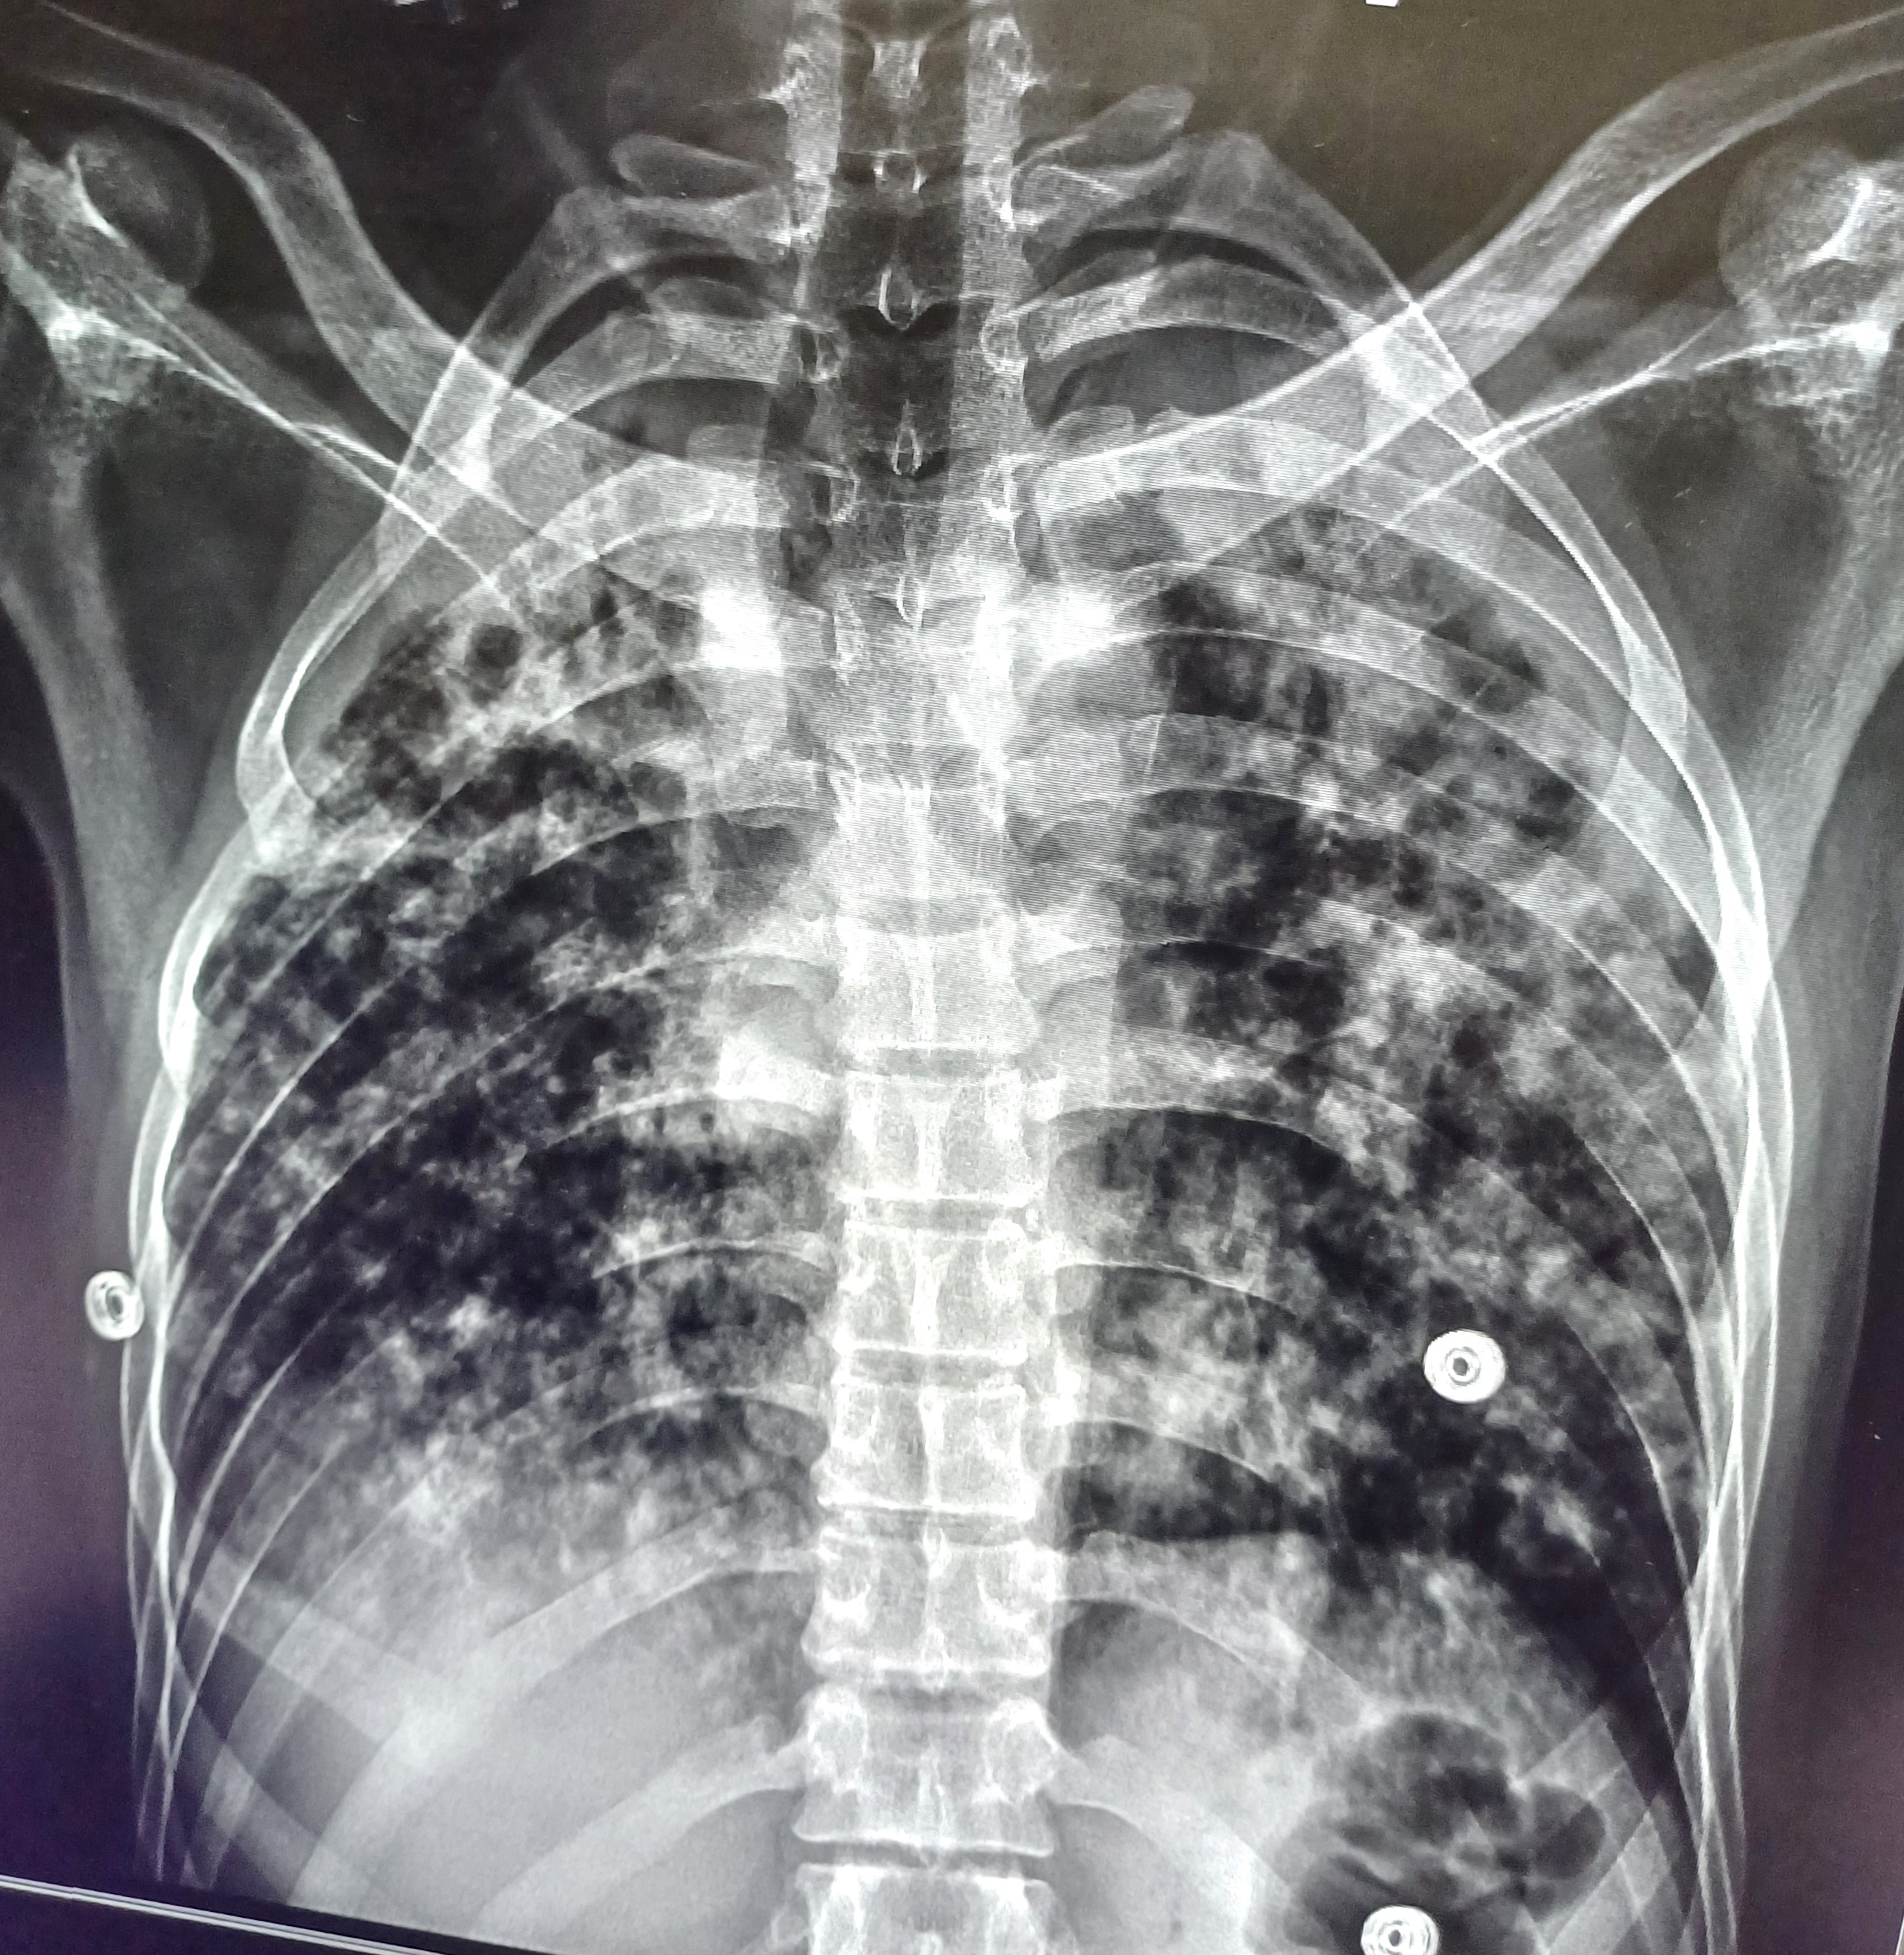

| 31 | IGGMC, Nagpur, Nagpur | P2 | 29-4441 | Shaina Parveen | Consent taken on Paper | 52 Yrs. |

Provisional Diag : Post TB Treatment Follow-Up

Final Diag : Pulmonary Tuberculosis (clinically diagnosed PTB) |

TB Case (Confirmed) | Bilateral Multiple Ill-Defined Opacity Present, Hyper Infiltration Present, Bilateral Lower Zone Haziness Present | Abnormality visible on x-ray |

View |

|||